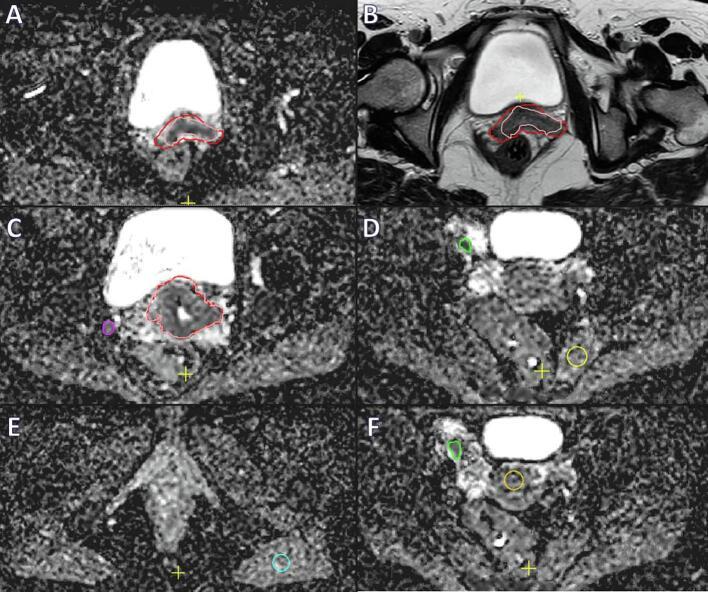

Twenty patients were included who received chemoradiation for locally advanced cervical cancer between July 2016 and November 2017. All patients underwent magnetic resonance imaging (MRI) prior to treatment, and three MRIs in weeks 1/2, 3 and 4 of treatment, including T2 and diffusion weighted imaging (values 0, 200, 800 s/mm) for determining an ADC-map. Primary tumour was delineated on T2 and ADC-map and pathologic lymph nodes were delineated only on ADC-map.

材料与方法

纳入20例在2016年7月至2017年11月期间接受局部晚期宫颈癌放化疗的患者。所有患者在治疗前均接受磁共振成像(MRI)检查,并在治疗的第1/2周、第3周和第4周进行三次MRI检查,包括T2加权成像和扩散加权成像(值为0、200、800 s/mm²)以确定ADC图。在T2加权成像和ADC图上勾勒出原发肿瘤,仅在ADC图上勾勒出病理淋巴结。